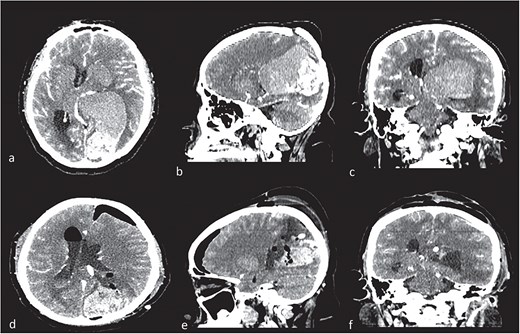

A 56-year-old female patient with a surgical history of drainage of a left parietal subdural hematoma 3 months prior to the current condition. The hematoma was spontaneous and was resolved by drainage without complications. In addition, the patient had a history of paraphasia, occasional headaches, and echolalia 1 month prior to her current condition. Fifteen days prior to her admission, a fine needle biopsy was performed on the thyroid due to a neck lesion with increased volume and pain. The pathology study reported papillary carcinoma of the thyroid. She was admitted as scheduled for thyroidectomy and wide neck resection. Upon admission, she presented sudden neurological deterioration, intense headache, motor aphasia, and weakness of the right side of the body. An urgent simple and contrast-enhanced cranial tomography was performed with the following findings (Fig. 1).

Contrast computed tomography (CT). (a–c) Intraventricular tumor, with a high volume, with the lateral ventricle shape. Different density in the tumor meaning intratumorally hemorrhage. (c–e) Control CT with resection of low-density lesion.

Given the presence of hemorrhage from a probable metastatic lesion on the left parietal, it was decided to undergo craniotomy and tumor resection. It was decided to perform an approach on the previous parietal craniotomy. The patient was placed in the concorde position, and the previous incision was extended. Likewise, the previous craniotomy was extended toward the occipital base. A transulcal posterior parietal approach was performed. The ventricular ependyma was found 5 mm from the parietal cortex, which was opened, and black, chocolate-colored liquid from the left lateral ventricle was found. A dark brown lesion was also observed, adhered to the walls of the lateral ventricle, toward the thalamus, floor of the ventricle, ventricular atrium, and multiple implant areas toward the choroid fissure, choroid plexus, and choroid artery. A subtotal resection was performed since the solid portion of the tumor was found with abundant blood vessels and adhered to the choroid plexus, with abundant bleeding (Fig. 2). The histopathological report confirmed a metastatic lesion in the brain of the thyroid papillary gland. The patient improved neurologically in the immediate postoperative period and was discharged 2 days later with improved consciousness and strength. She continued her oncological treatment, and treatment of the cranial metastatic lesion was complemented with radiotherapy (Fig. 1).